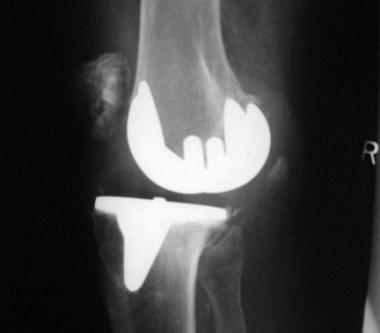

Fine attention to general operating technique with adroit handling of tissues and efficient teamwork (see the image below) can reduce operating time to a minimum and thus avoid exposing the wound for an inordinate amount of time. An experienced, efficient technique also aids in preventing deep venous thrombosis (DVT) and unnecessary scarring and decreases the incidence of many of the complications that are associated with TKA.

Total knee arthroplasty. Implanted knee with excellent insertion.